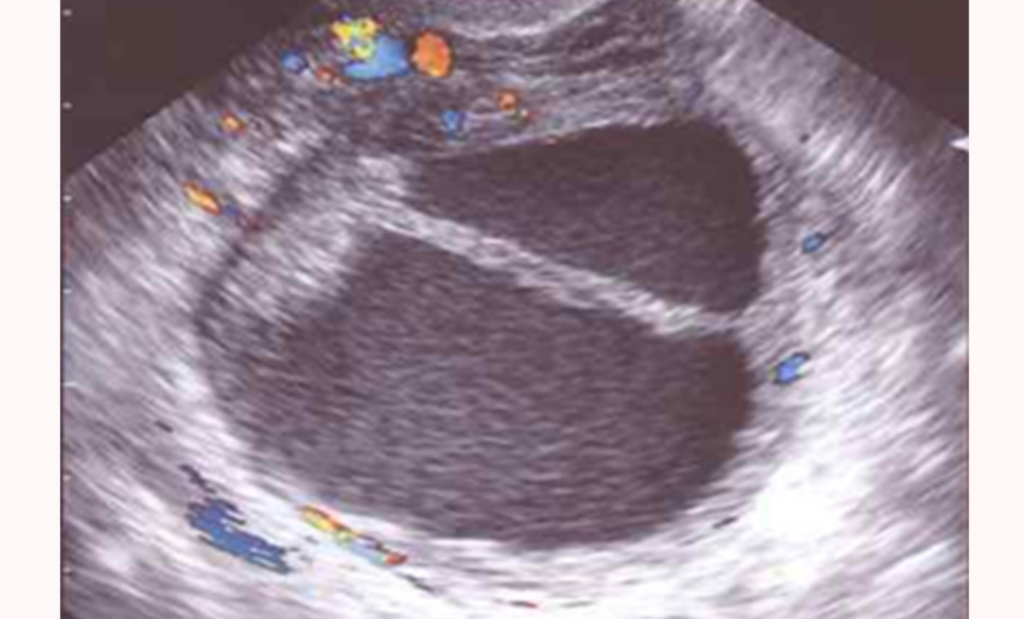

Durante el ciclo menstrual de una mujer, un óvulo crece en una bolsa llamada folículo; Los quistes ováricos son sacos llenos de líquido en o sobre un ovario. Estos quistes pueden ser foliculares o de cuerpo lúteo y, generalmente, desaparecen a las semanas sin ninguna intervención. Se puede detectar un quiste en el ovario durante un examen pélvico o en una prueba por imágenes, como una ecografía pélvica. Los quistes son sacos llenos de líquido que pueden aparecer sobre o en cualquier área del cuerpo. Generalmente, se forman durante la ovulación,. ¿cuáles son los síntomas de los quistes de ovario? Los quistes ováricos pueden aparecer en el transcurso del ciclo menstrual normal, dando lugar a los quistes funcionales. El quiste ovárico es una lesión que, cuando pequeña, generalmente no causa síntomas y puede desaparecer espontáneamente con el. ¿qué son los quistes de ovario?

¿Qué es el quiste de ovario? Síntomas, causas y cómo tratar la enfermedad Como Salen Los Quistes De Los Ovarios Se puede detectar un quiste en el ovario durante un examen pélvico o en una prueba por imágenes, como una ecografía pélvica. ¿qué son los quistes de ovario? La bolsa se localiza en el. Los quistes ováricos pueden aparecer en el transcurso del ciclo menstrual normal, dando lugar a los quistes funcionales. Durante el ciclo menstrual de una mujer, un. Como Salen Los Quistes De Los Ovarios.